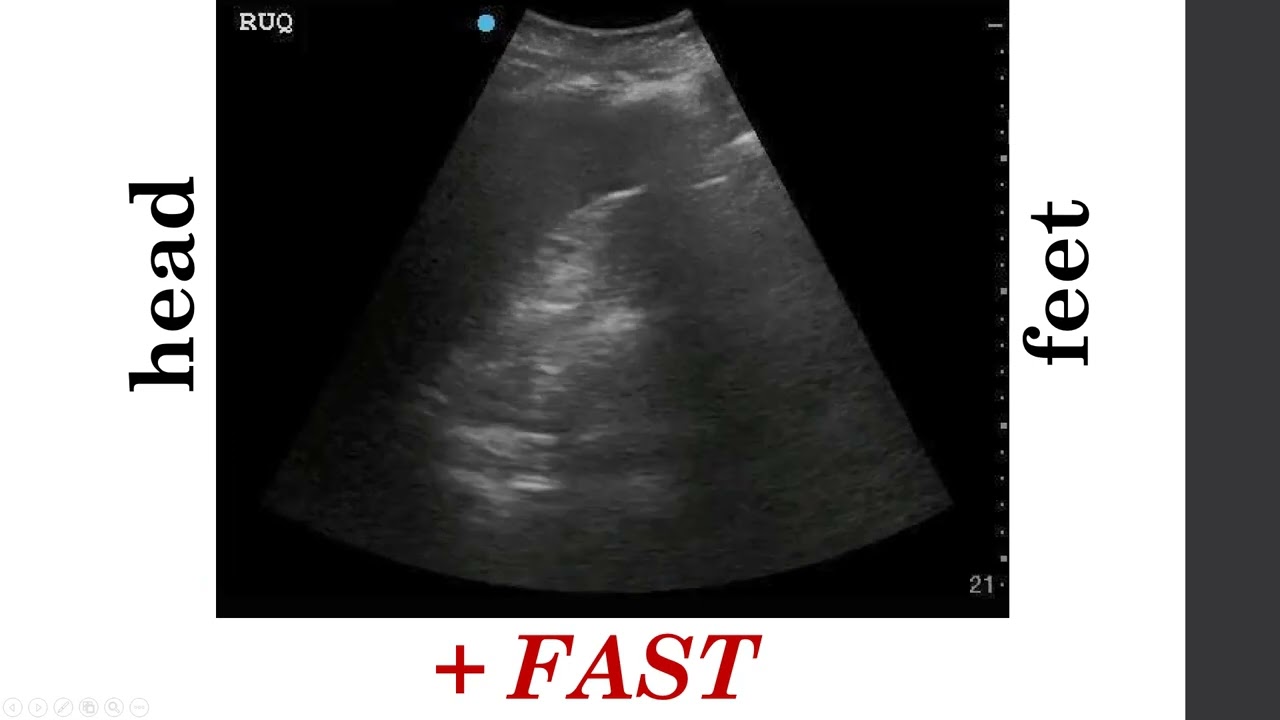

Introduction to eFAST Ultrasound for Medical Students

Presented by Dr. Hani Kuttab (Phase 2, SPC Students. 1/2022)